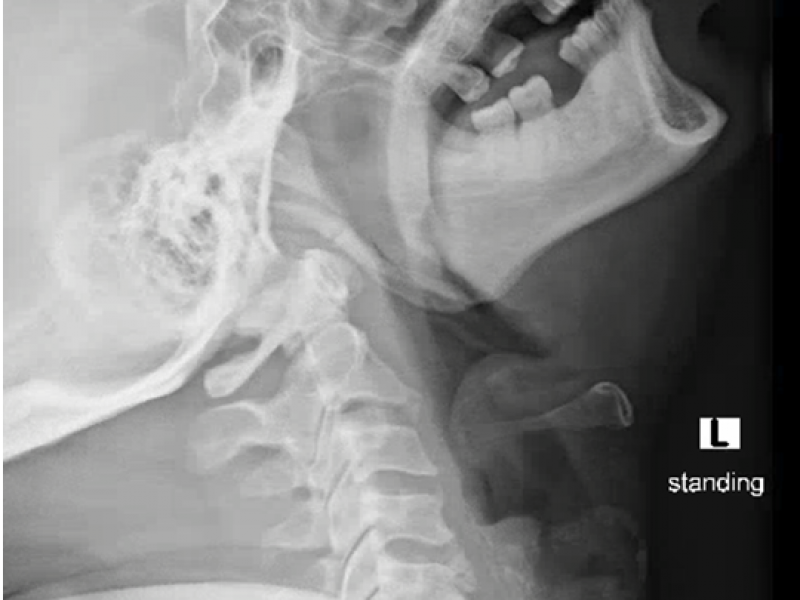

A 53 yo M presents to the ED with 3 days of a severe sore